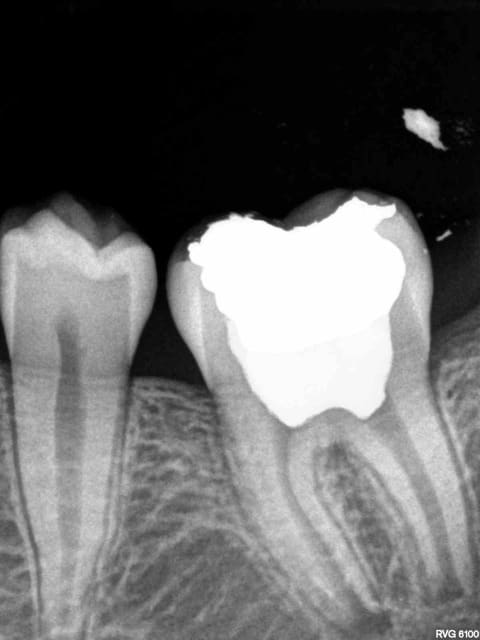

On découvre les subtilités au fur et à mesure. Par exemple pulpo sur dent immature hbfd 032 NPC et non pas hbfd 006 (dent de lait).

Pulpite hvjaqs - Eugenol

Pulpo hbfd 032 lyjokh - Eugenol